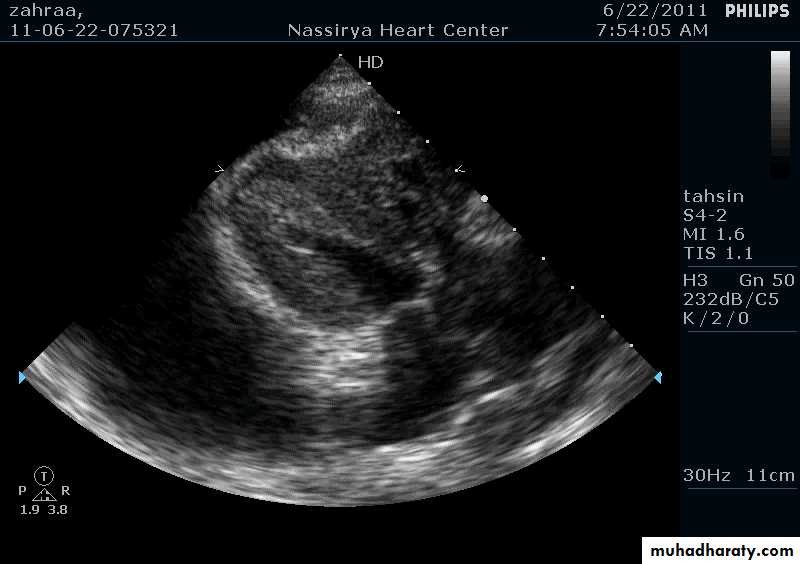

Echocardiography

Thickening of pericardiumPericardial effusion

Pericardial Effusion: Investigation

Echocardiography: establishes the diagnosis31